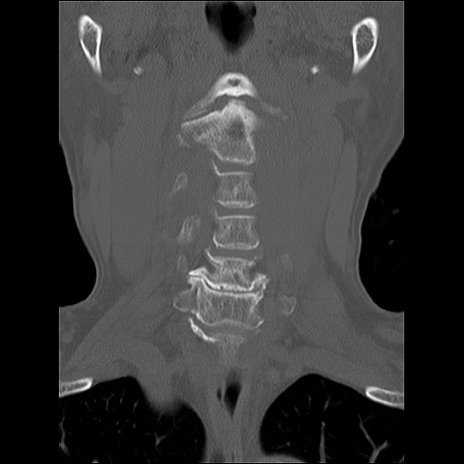

症例48 頚椎CT(冠状断像)

頚椎CT